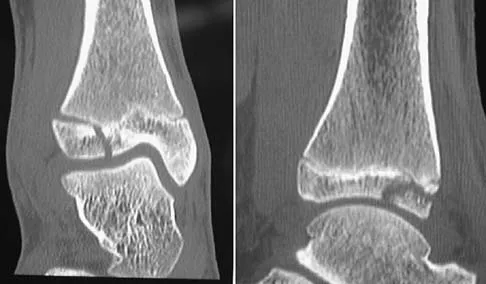

A 13-year-old girl injures her ankle playing soccer. Radiographs reveal a displaced Tillaux fracture. CT scans are shown in Figure 25. What is the most important consideration for appropriate management?

Explanation